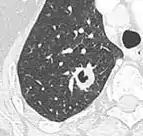

Thin slice and maximal intensity projection of a lung nodule, the latter better visualizing vascular convergence.[9]

• Vascular convergence is where vessels converge to a nodule without adjoining or contacting the edge of the nodule, and is mainly seen in peripheral subsolid lung cancers.[9] It reflects angiogenesis.[9]